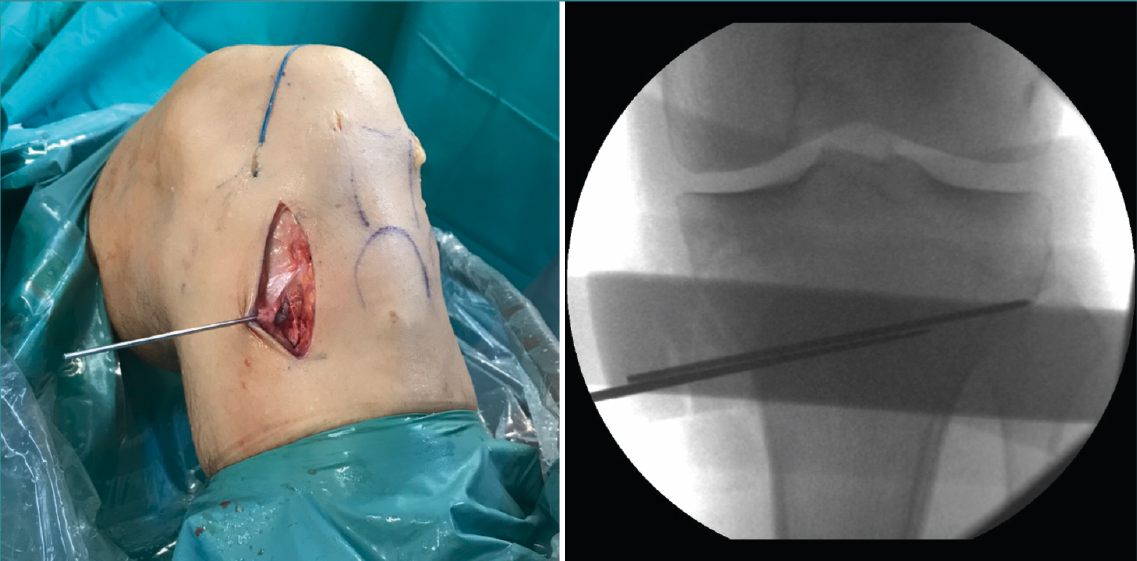

Figura 2. Colocación de aguja guía: punto de entrada en la unión metafisodiafisaria tibial dirigida hacia la cabeza del peroné.

Una vez disecado el plano subcutáneo, se identifica la pata de ganso y se extraen los isquiotibiales según la técnica habitual de cada cirujano (Figura 1B). Bajo control radioscópico, se coloca la aguja guía aproximadamente medio centímetro por encima de la pata de ganso orientada hacia la cabeza del peroné, según la técnica clásica de osteotomía biplanar (Figura 2). Se marcan los cortes de la osteotomía biplanar y se realiza primero el corte vertical por encima de la tuberosidad tibial, con una inclinación de aproximadamente 120° respecto a la osteotomía de apertura llegando hasta la cortical lateral (Figura 3).

Figura 3. Se marcan los cortes de la osteotomía biplanar con un ángulo de 120°.